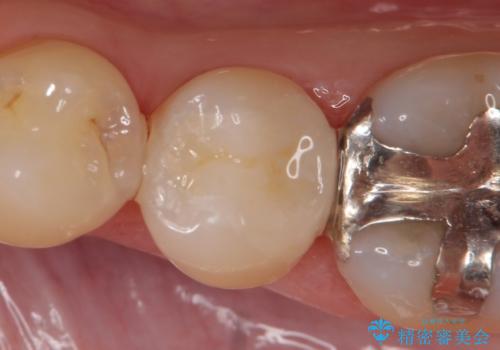

- 右下7の銀歯が外れてしまった方の症例です。

古い樹脂やカリエスを除去後、形を整え、オールセラミッククラウンによる補綴を行いました。